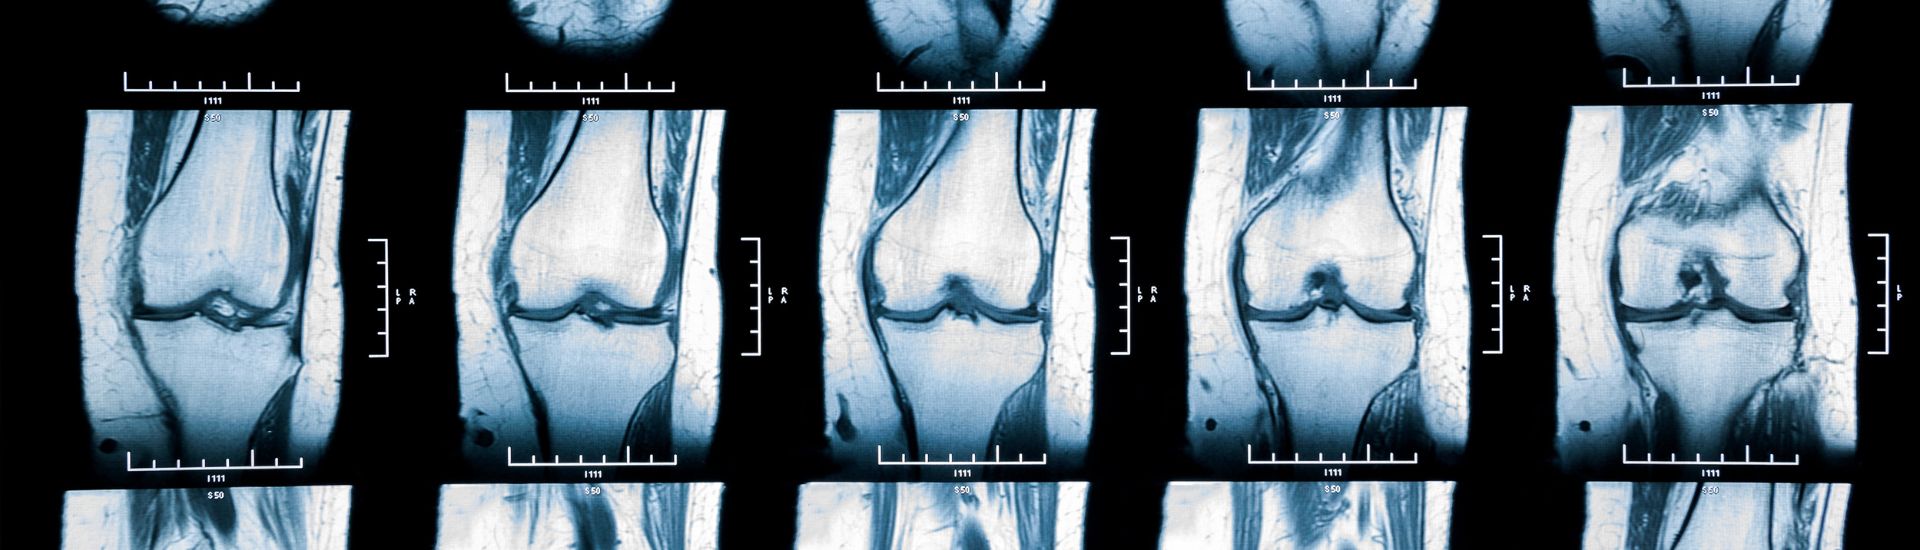

La Risonanza Magnetica Ginocchio permette ai medici di osservare con precisione le strutture anatomiche del ginocchio. Le immagini dettagliate rivelano lo stato dei legamenti, dei tendini, dei muscoli e delle cartilagini, facilitando una valutazione complessiva dell’articolazione.

La Risonanza Magnetica Ginocchio presso il Poliambulatorio S-Medical Group di Sora è un’importante risorsa diagnostica per valutare l’articolazione e identificare eventuali patologie. Con le tecnologie di imaging all’avanguardia, offriamo immagini dettagliate che consentono diagnosi e trattamenti precisi.